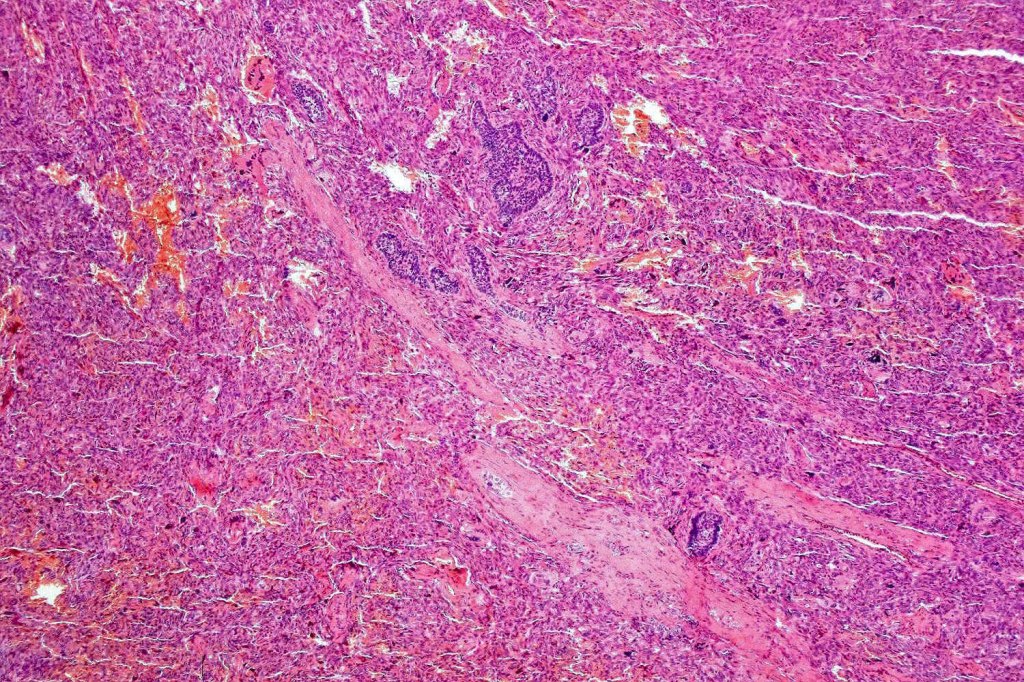

Carcinosarcoma

Cutaneous carcinosarcoma (metaplastic carcinoma, carcinoma with heterologous differentiation)

Histological features

•Osteoid

•Chondroid

•Smooth muscle

•MFH-like features with osteoclasts

•Neural differentiation